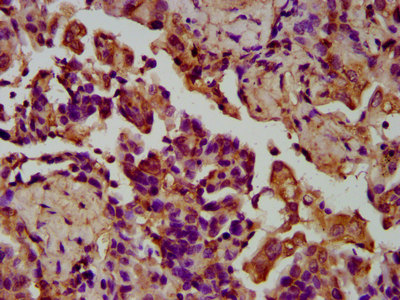

IHC image of CSB-PA818678LA01HU diluted at 1:200 and staining in paraffin-embedded human liver cancer performed on a Leica BondTM system. After dewaxing and hydration, antigen retrieval was mediated by high pressure in a citrate buffer (pH 6.0). Section was blocked with 10% normal goat serum 30min at RT. Then primary antibody (1% BSA) was incubated at 4°C overnight. The primary is detected by a biotinylated secondary antibody and visualized using an HRP conjugated SP system.